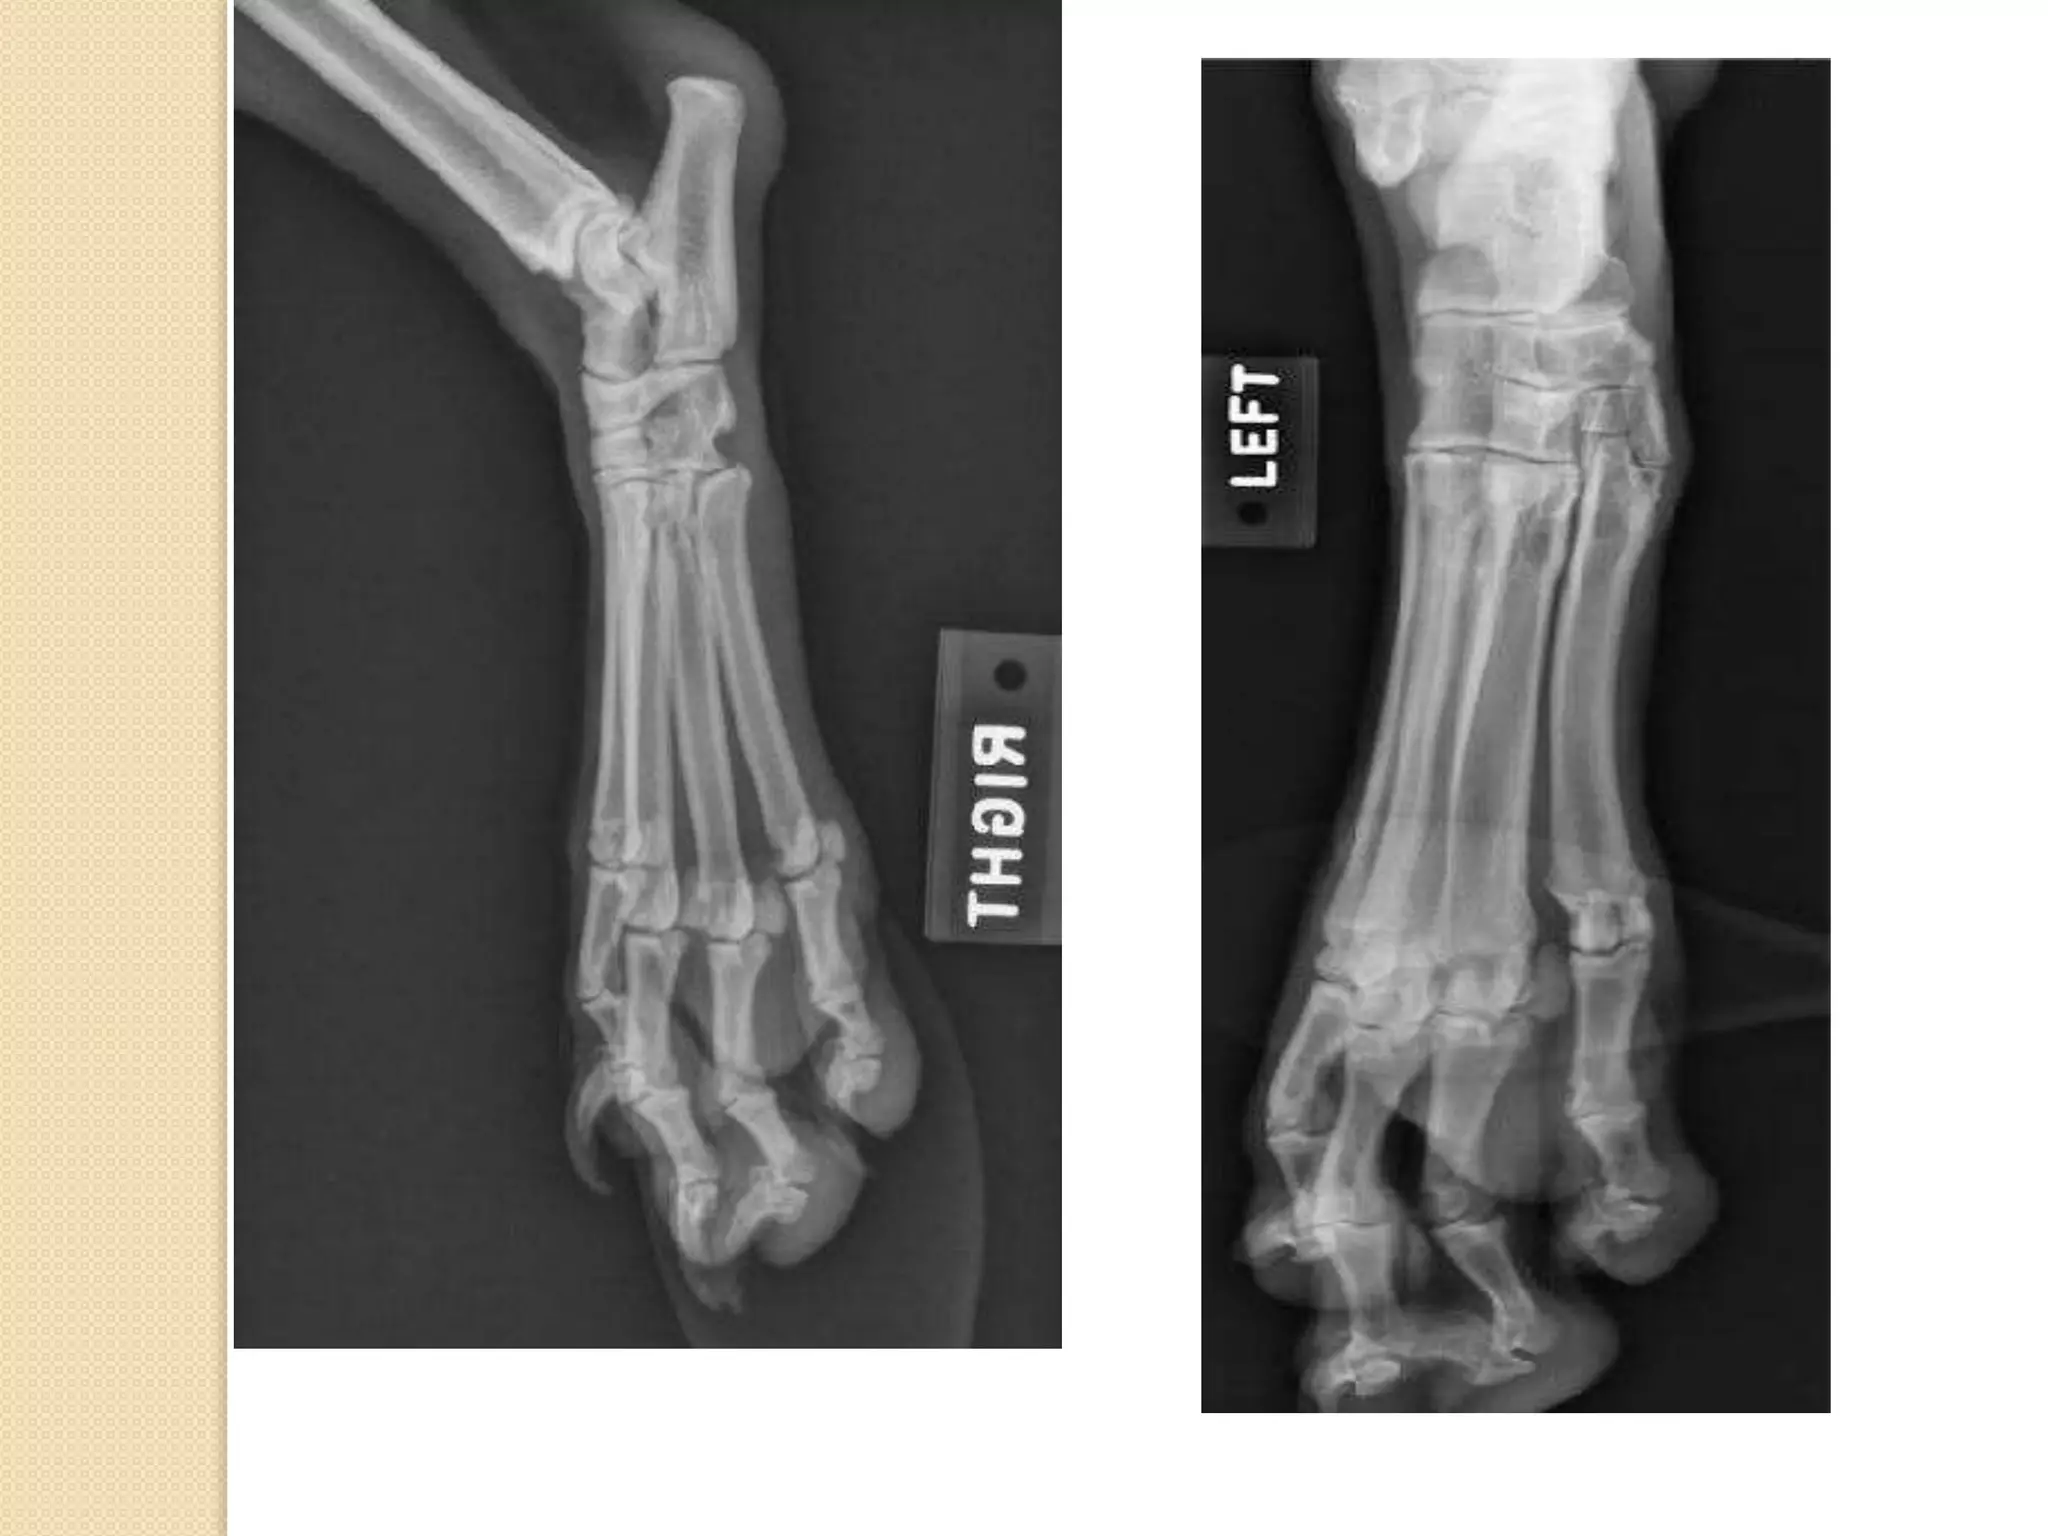

Carpus , metacarpus and

phalanges:

Carpus is a group of small bone which form the

wrist joint , it is arranged in rows which differ

from species to another .

No. of carpal bone : 7

No. of bones in the proximal row : 4

No. of bones in the distal row : 4

Metacarpal bones is a group of long bones

which form the palm in human hand, the number

of these bones differ from species to another.

No. of metacarpal bones : 5

The first one is the shortest while the III and IV is

the longest .

Phalanges is a group of 3 bones which form the

fingers ( except in the first finger 2 bones ) , they

are called 1st , 2nd ,3rd .

The 3rd phalange and the distal part of the 2nd

phalange is coverd by claws.